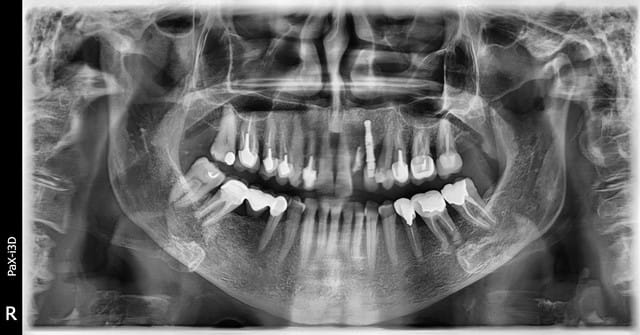

Bonsoir, je reçois ce jour une patiente qui a perdu une ccm sur sa 22 , cette 22 a déjà subi une résection apicale et il n' y a pas d'autres choix que d'extraire.

En 23 on a un implant qui semble bien ostéo intégré même si on remarque une forte perte osseuse sur la 24 mesial qui vient contaminer l'implant.

L'autre problème est que le cone bean révèle que l implant est en dehors de la crête osseuse

Il n'y a pas d'épaisseur pour poser un implant en 22 sans envisager une greffe au préalable.

Que faire de l'implant 23 ?